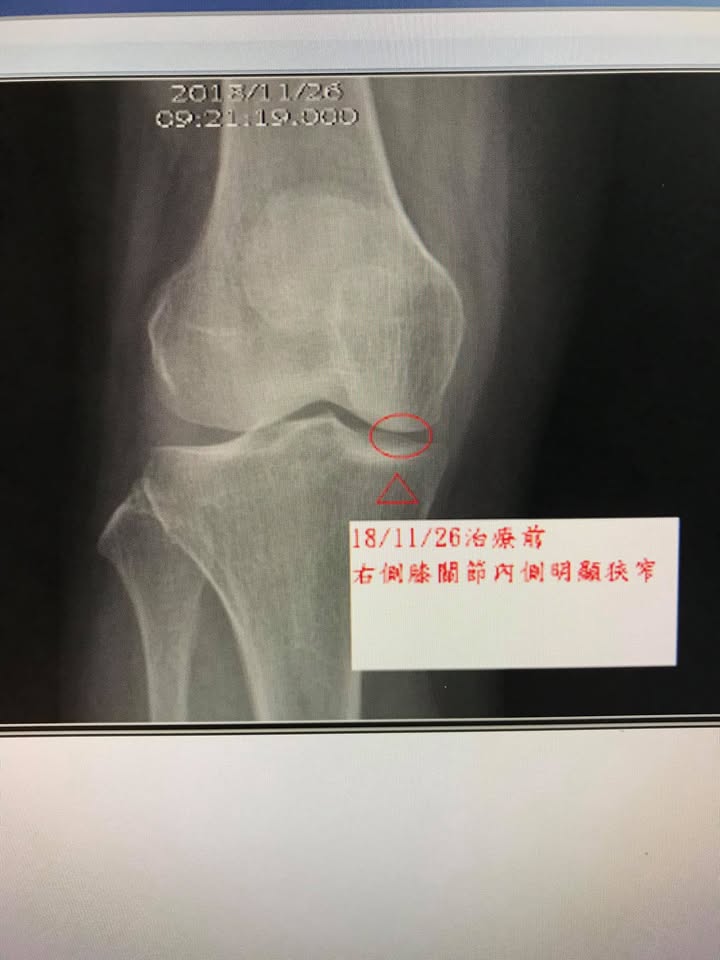

😭游大姊,年約五十多歲,右膝疼痛超過五年,之前在宜蘭當地骨科拍片檢查退化性膝關節炎,症狀如下:走久會痠痛,外側膝蓋很緊,平常膝關節內側明顯刺痛,可以免強蹲下來,上下樓梯很不舒服,特別是下樓梯,都要慢慢扶著欄杆,在當地已經打過波尿酸跟三次自體血小板生長因子,也就是俗稱的PRP,有一點效果,但這幾個月又開始非常痛,在榮總蘇澳分院拍片子檢查發現右側膝關節內側明顯窄縮(如圖)合併左側膝關節臏骨外翻(如圖),經兒子朋友介紹特地來接受膝關節針刀整合治療